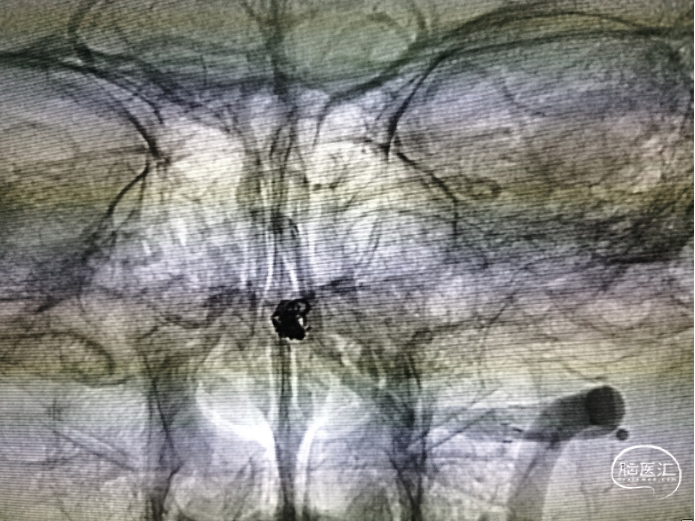

穿支架网眼动脉瘤近全栓塞(Target 360 Ultra 3 mm×6 cm、Target 360 Ultra 2 mm×6 cm

Gateway 2.0 mm×15 mm球囊命名压缓慢后扩支架

栓塞结束后造影情况,可见支架贴壁良好,血管狭窄较前改善,动脉瘤近全栓塞,远端大脑后动脉显影明显改善